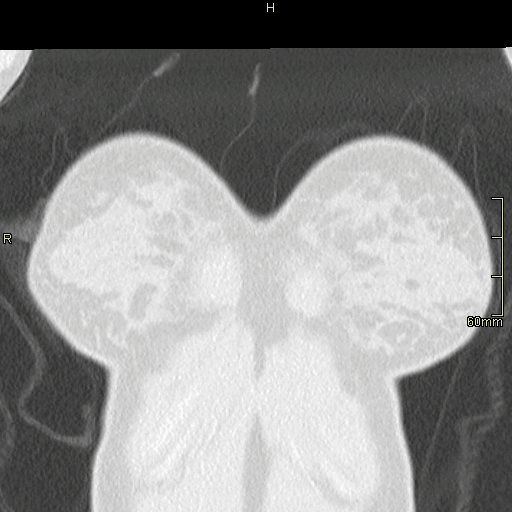

CTPA (Axial)

CTPA (Coronal)

Lung (Coronal)